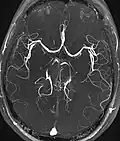

| Angiografia e venografia por Ressonância Magnética (MRA) | Voo de tempo | TOF | O sangue que entra na área de imagem ainda não está saturado magneticamente, dando um sinal muito mais alto ao usar tempo de eco curto e compensação de fluxo. | Detecção de aneurisma, estenose ou dissecção.[89] | ![]() |

| Ressonância magnética com contraste de fase | PC-MRA | Dois gradientes com magnitude igual, mas direção oposta, são usados para codificar uma mudança de fase, que é proporcional à velocidade das rotações.[90] | Detecção de aneurisma, estenose ou dissecção.[91] | ![]() |